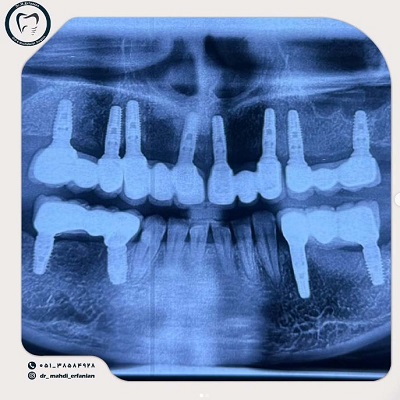

دکتر مهدی عرفانیان تقوایی

دکتر مهدی عرفانیان تقوایی، متخصص جراحی های زیبایی و ترمیمی دندان و از برجستهترین جراحان در زمینه جراحیهای پیچیده فک و زیبایی دندان مانند پروتز فک هستند. با دانش و تجربه فراوان، ایشان درمانهایی دقیق و نتایجی طبیعی و ماندگار برای بیماران ارائه میدهند.

- کاشت ایمپلنت دیجیتال

- نصب و طراحی پروتز فک

- درمان کیست و تومورهای فک

- اصلاح ناهنجاری های مادرزادی فک و صورت

مشهد، چهارراه دکترا، روبه روی پارکینگ طبقاتی بیمارستان امام رضا)، نبش ابن سینا 7، ساختمان پزشکان سینا ، طبقه 4، واحد 401